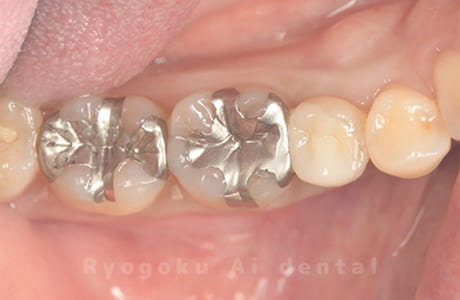

Case11

- 治療内容

- セラミッククラウン、セラミックインレー

-

- 治療費用

- 123,000円×2(セラミッククラン)、77,000円(セラミックインレー)

銀歯が取れて、ご来院された患者様です。奥歯2本をセラミッククラウン、手前の小臼歯をセラミックインレーで治療を行いました。